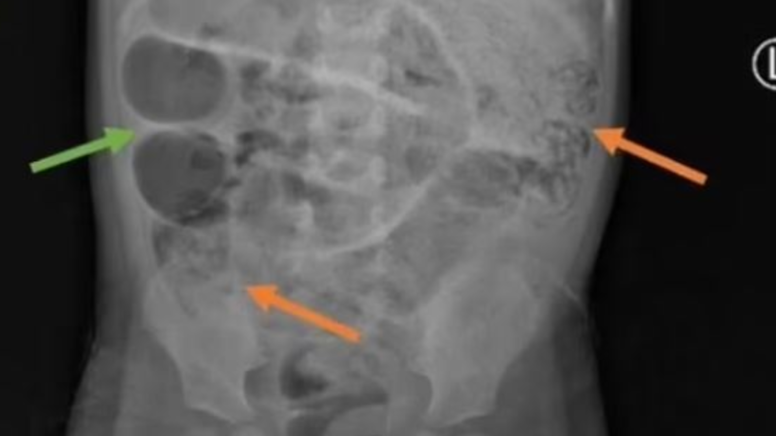

Endonezya’da aylarca mide ağrısı, kabızlık ve ateşlenme sorunu yaşayan 3 yaşındaki çocuk, bir süre sonra kurt kusmaya başladı. Karın şişliği ile hastaneye kaldırılan çocuğa röntgeni çekildi. Gri kitlelerin görüldüğü röntgende kurtların ince bağırsağın üç ayrı bölgesini tıkadığı ortaya çıktı.